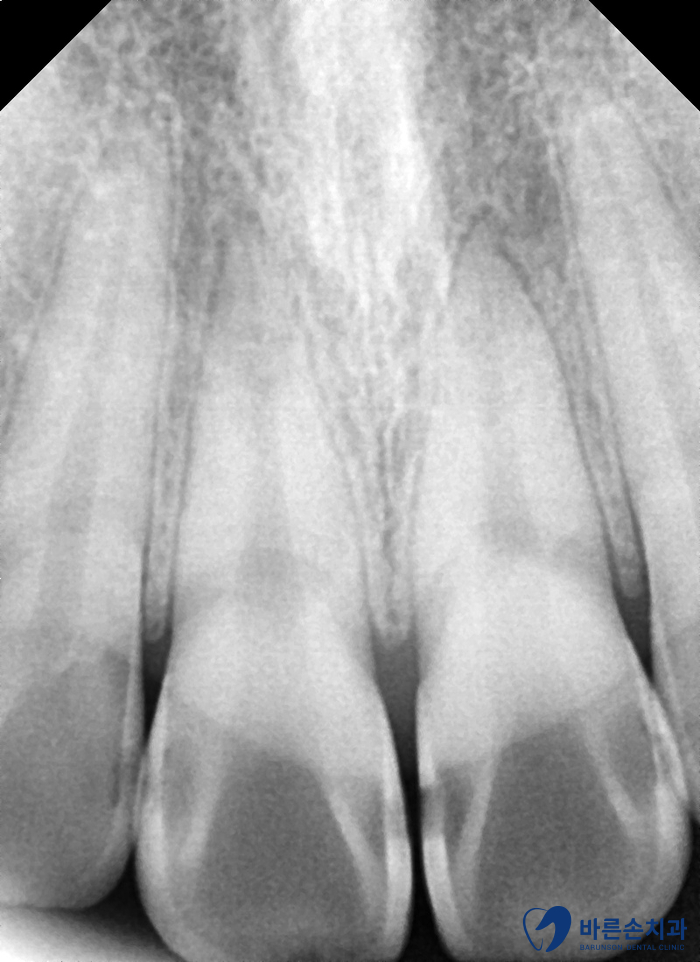

먼저 치아 사진을 찍어보니 앞니 사이사이에 충치가 생겼네요!

이미 까맣게 비춰보일 정도라 충치가 꽤 진행된 상태였습니다.

정밀한 진단을 위해 엑스레이도 촬영 해보았습니다.